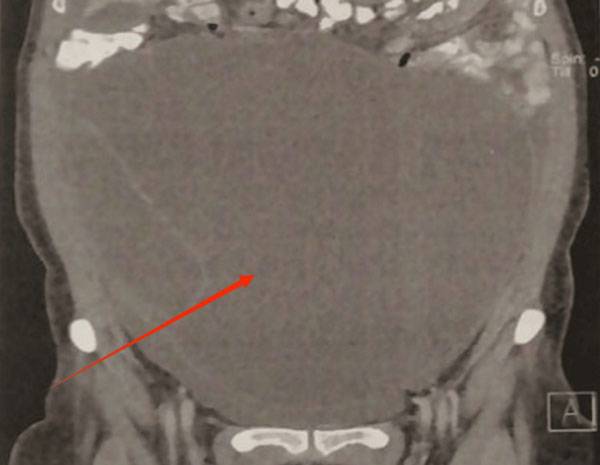

그리스 아테네 국립 카포디스트리아대(National and Kapodistrian University of Athens) 해부학과 의료진은 별다른 문제 증상이 없었던 61세 여성 A씨가 정기 건강 검진에서 거의 복부 전체를 차지할 정도의 큰 난소 종양이 발견됐다고 밝혔다. A씨는 최근 1년간 체중과 복부 둘레가 늘긴 했지만, 그 외에 다른 증상은 없었다고 했다.

의료진은 난소 종양을 제거하기 위한 개복술을 시행했고, 실제 뱃속에서 25cm에 달하는 거대 종양이 발견돼 제거했다. 더불어 전체 자궁을 적출하고, 양측 난관과 난소를 제거하는 등의 수술도 진행됐다. 조직병리학 검사 결과, 문제가 된 낭종은 크기가 25cm x 18cm x 16cm에 달했고, 무게는 4kg로 확인됐다.